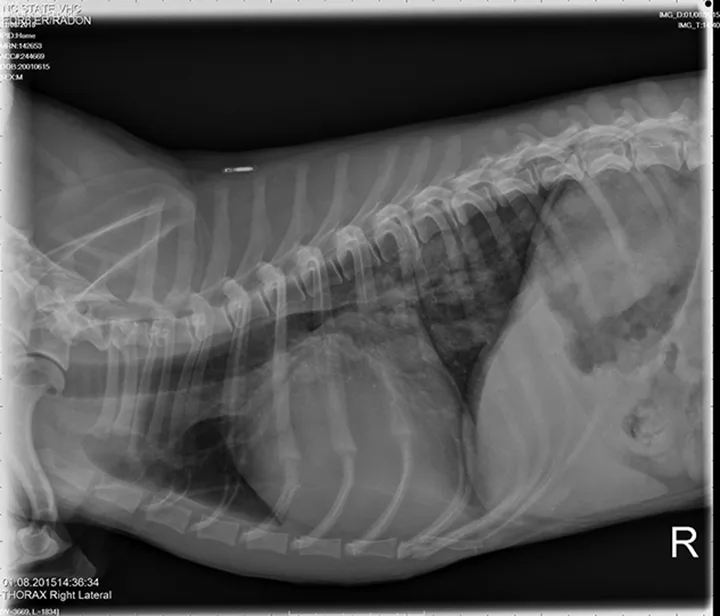

A grade IV/VI systolic heart murmur was detected with a point of maximal intensity over the left apical region; heart rhythm was regular, and pulses were strong and synchronous. Lung sounds were increased, with no crackles or wheezes. Thoracic radiographs showing progressive left atrial and ventricular enlargements, mildly enlarged pulmonary veins, a moderate patchy unstructured interstitial pattern in the right caudal lung lobe, and a mild unstructured interstitial pattern in the left caudal lung lobe were consistent with pulmonary edema. Caudal mainstem bronchi were compressed on lateral projections secondary to the cardiomegaly and left atrial enlargement. Radiographic findings were compatible with left-sided congestive heart failure (CHF) secondary to MV disease.

Lateral and DV views showing mild CHF in a dachshund with mitral valve disease.